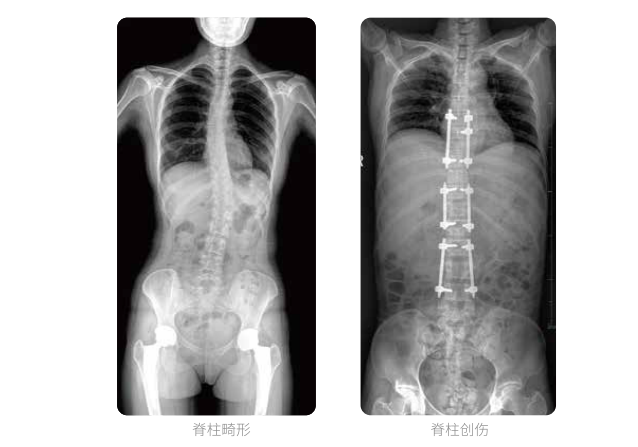

全脊柱臨床影像

普愛醫療動態數字化X線攝影(動態DR)可以使整個脊柱一次成像,直觀顯示脊柱的整體形態以及側彎部位,評價側彎的病理程度,全面了解脊柱各個階段的生理曲度及椎間關節連接的關系,避免了常規脊柱攝影對整個脊柱曲度的影響。為脊柱側彎的診斷治療提供了重要的影像學依據。

動態數字化X線攝影(動態DR)成像